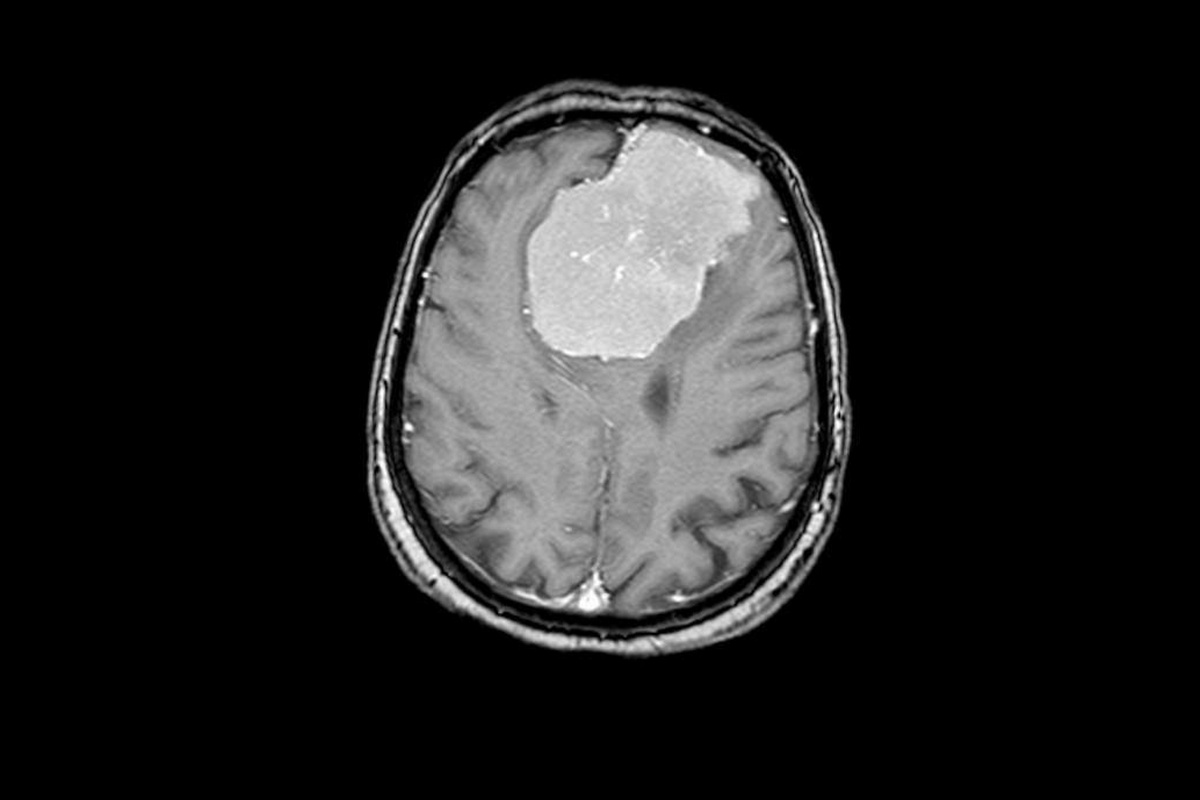

Нейрохирурги Воронежской городской больницы скорой медицинской помощи (БСМП) №1 провели 80-летней пациентке сложную 6-часовую операцию по удалению опухоли мозга, которая достигла размеров грейпфрута – 6 х 7 х 8 см. Главной задачей врачей было не только удалить новообразование, но и сохранить здоровье пожилой женщины – не повредить жизненно важные сосуды и участки мозга, чтобы избежать осложнений. Медиков ждал успех. Сейчас пациентка уже выписана, послеоперационный период у пенсионерки проходит хорошо, она обслуживает себя самостоятельно. Неврологическая симптоматика спала сразу после хирургического вмешательства. Об этом случае рассказали в региональном министерстве здравоохранения в среду, 21 мая.

Пенсионерка поступила в БСМП №1 с подозрением на инсульт. У женщины наблюдались проблемы с речью и слабость в правой руке. После стандартного обследования с помощью компьютерной томографии выяснилось, что инсульта у нее нет. Однако в обеих лобных долях мозга была обнаружена опухоль.

– Подобные новообразования так или иначе затрагивают важные участки мозга – кровеносные сосуды и зоны, отвечающие за речь и движение. Дополнительное исследование с контрастом показало, что опухоль окутывала магистральные сосуды Виллизиева круга – переднюю мозговую артерию, а также прорастала в переднюю треть сагиттального синуса (один из наиболее крупных венозных коллекторов головного мозга) и закрывала его, – разъяснили медики.